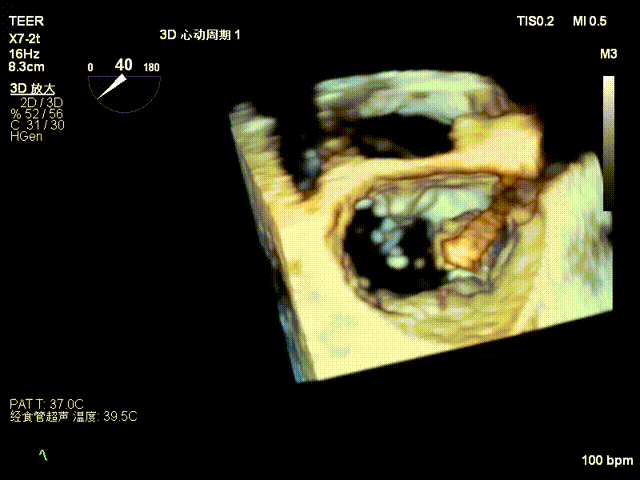

3D

3D彩色